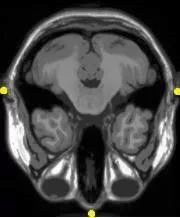

图像配准在医学图像处理与分析中有众多具有实用价值的应用。随着医学成像设备的进步,对于同一患者,可以采集含有准确解剖信息的图像诸如CT,MRI;同时,也可以采集到含有功能信息的图像诸如SPECT。然而,通过观察不同的图像进行诊断需要凭着空间想象和医生的主观经验。采用正确的图像配准方法则可以将多种多样的信息准确地融合到同一图像中,使医生更方便更精确地从各个角度观察病灶和结构。同时,通过对不同时刻采集的动态图像的配准,可以定量分析病灶和器官的变化情况,使得医疗诊断、制定手术计划、放射治疗计划更准确可靠。

③Multi-modal Analysis: 多模态配准

多模配准常见于医学图像领域,故以多模医学图像配准为例。

由于医学成像设备可以提供关于患者不同信息不同形式的图像(计算机断层扫描CT,核磁共振MRI,正电子发射断层成像PET,功能核磁共振fMRI等)。

基于单种或多种模态图像的配准,可划分为单模态(Single-modality)和多模态(Multi-modality)。